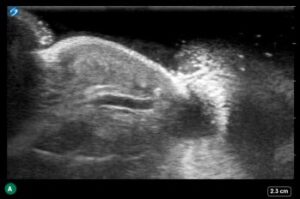

Figure 1: Soft tissue point-of-care ultrasound showing fluid surrounding the flexor sheath at the left middle finger (A) and right thumb (B and C).